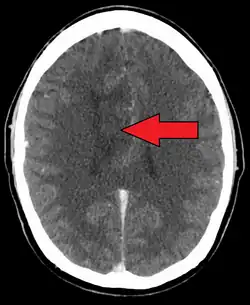

A oligoastrocytoma on CT | |

An X-ray computed tomography (CT) or magnetic resonance imaging (MRI) scan is necessary to characterize the anatomy of this tumor as to size, location, and its homogeneity and heterogeneity. However, final diagnosis of this tumor, like most tumors, relies on histopathologic examination (biopsy examination).[4]